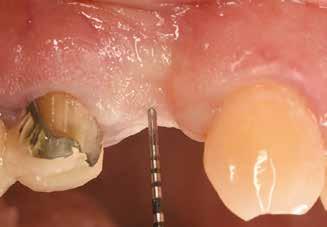

Az eljárást helyi érzéstelenítés mellett végeztük (4%-os articaine-hidroklorid 1:100 000 adrenalinnal). Papillakímélő, U alakú palatális bemetszést végeztünk, teljes vastagságú nyálkahártyalebeny preparálás történt, a lebenyt bukkálisan feltekertük (5. ábra). A lebeny bukkálisan feltekert részén de-epitelizációt végeztük el, amellyel kompenzálni tudtuk a bukkális lágyszöveti defektust. Szakaszos előfúrást végeztünk, és a bredent copaSKY 4x10 implantátumot 30 Ncm behajtási nyomatékkal helyeztük be (6. ábra). Az implantátumot 1 mm-re szubkresztálisan helyeztük be, hogy később szélesebb emergenciaprofilt tudjunk kialakítani (7. ábra). Az egyedi ínyformázó úgy készült, hogy kompozitot vittünk fel a titánbázisra, és így formáztuk a lágyszöveteket a transzgingivális gyógyulási fázis során (8. ábra). Az egyéni ínyformázó tulipán formájú, hogy kialakítsa a kívánt emergenciaprofilt. A lágyszövetet feszülésmentesen zártuk #6/0 nem felszívódó, monofil fonallal (Optilene, B. Braun Deutschland; 9. a–b. ábra). Posztoperatív röntgenfelvétel készült, ami alapján az implantátum a szomszédos fogakkal párhuzamos elhelyezést mutatott (10. ábra). Posztoperatív utasításokat adtunk a páciensnek a műtéti terület körüli szájhigiénia fenntartása érdekében. A beavatkozást követő egy héttel a varratokat eltávolítottuk, és a kezelt terület kielégítő gyógyulást mutatott (11. ábra). A 4 hónap utáni késleltetett terhelést a páciens kívánsága szerint terveztük.

10. ábra: A műtét utáni radiológiai felvétel.

11. ábra: Varrateltávolítás egy hét után, kielégítő gyógyulás látható.

12. a. ábra: Biológiai szélesség 5 mm.

12. b. ábra: Okkluzális nézet négy hónappal a műtét után, amely megfelelő bukkális lágyszövetvastagságot mutat.

13. ábra: Négy hónap elteltével a szájüregben látható marginális zenit megmaradt.

14. ábra: Egészséges implantátum körüli lágyrészgallér.

uni.fit titánalapra (bredent medical). Az implantátum körül a bukkális lágyszövet megfelelő vastagságot és kedvező ínykontúrt mutatott (12. a–b. ábra). Az egyedi ínyformázó eltávolítása után egészséges implantátum körüli lágyrészgallér

volt megfigyelhető (13–14. ábra), ezen kívül közvetlenül a műtét előtt intraorális vizsgálatot végeztünk a lágyszöveti profil megállapítása érdekében. Ezt követte a scanbody behelyezése, így digitális lenyomat készült az implantátum pozíciójáról (15. ábra). Ugyanezzel a technikával rögzítettük az antagonista fogívet és a harapást is. Az így kapott STL-fájlokat digitálisan továbbítottuk a fogtechnikai laboratóriumba. A titánalapra PMMA ideiglenes koronát készítettünk a proximális és marginális illeszkedés ellenőrzése érdekében, valamint a megfelelő harapás elérése céljából (16–17. ábra) Miután az összes igazítás elkészült, ismételt vizsgálatot végeztünk. A végleges hibrid csavarrögzítésű, teljes kontúrú cirkóniumkoronát titánalapon erősen polírozott szubgingivális résszel készítettük el, és 25 Ncm nyomatékra húztuk (18. ábra). Kiváló árnyalategyezést és klinikai eredményt